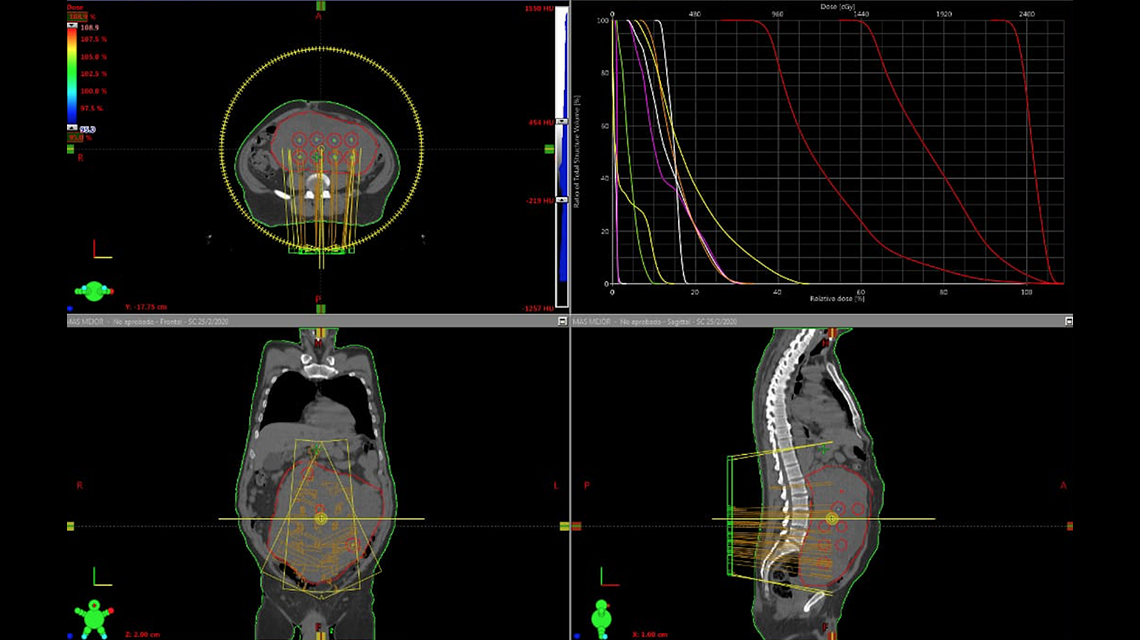

There have been a number of advances in radiotherapy in recent years, including: stereotactic radiotherapy, intensity modulated radiation therapy, image-guided radiation therapy, motion management techniques, magnetic resonance imaging-guided linear accelerators, three-dimensional conformal brachytherapy, proton therapy and light ion therapy, to name but a few. However, access to high standard cancer care remains a global challenge.

• Developments in treatment planning

• Intensity modulated radiotherapy, including arc-based approaches

• Stereotactic radiotherapy